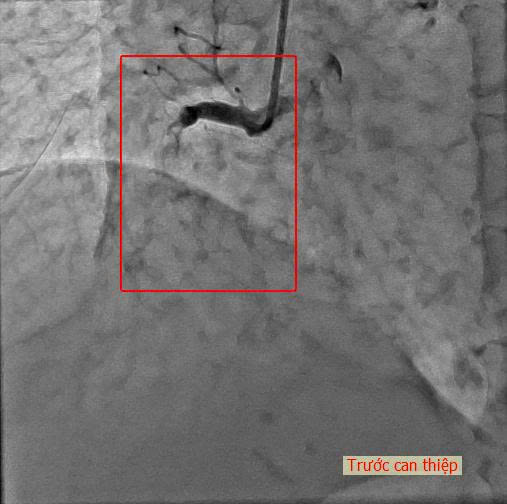

Cụ K. nhanh chóng được chuyển vào phòng DSA. Kết quả chụp mạch vành cho thấy hệ mạch vành của cụ bà vôi hóa nặng, một tình huống rất nguy hiểm ở người lớn tuổi, trong đó động mạch vành phải bị tắc hoàn toàn, nguyên nhân trực tiếp gây ra cơn nhồi máu cơ tim cấp.

Nhận định mức độ nguy kịch, ekip Can thiệp Tim mạch lập tức tiến hành tái thông mạch vành khẩn. Thủ thuật được thực hiện nhanh chóng và chính xác, stent được đặt thành công, dòng chảy mạch máu phục hồi tối ưu. Toàn bộ quá trình diễn ra an toàn, không ghi nhận biến chứng.

Hình ảnh sau can thiệp đặt stent